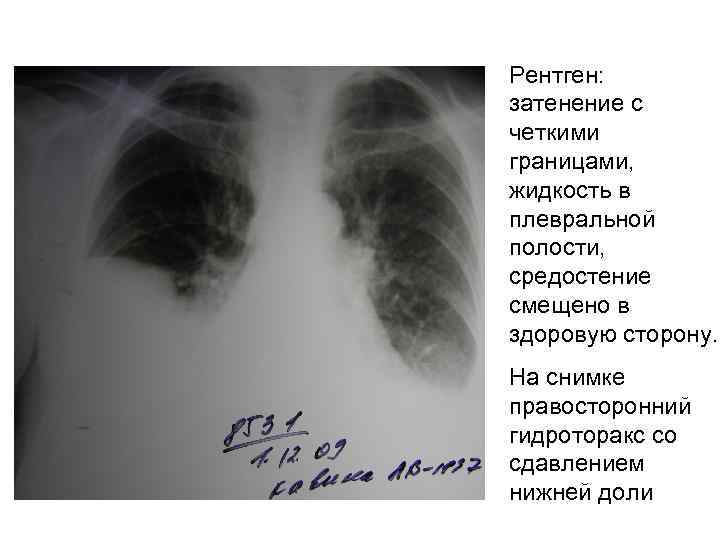

Диагностика плеврального выпота: что нужно знать